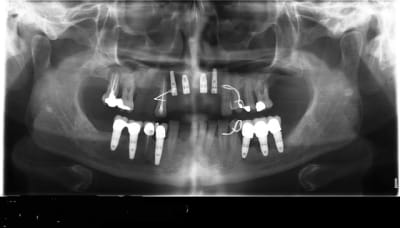

un an après !

ça s'arrange pas, voyez plutôt..

augmentation de la perte osseuse +++

7 les radios post-op